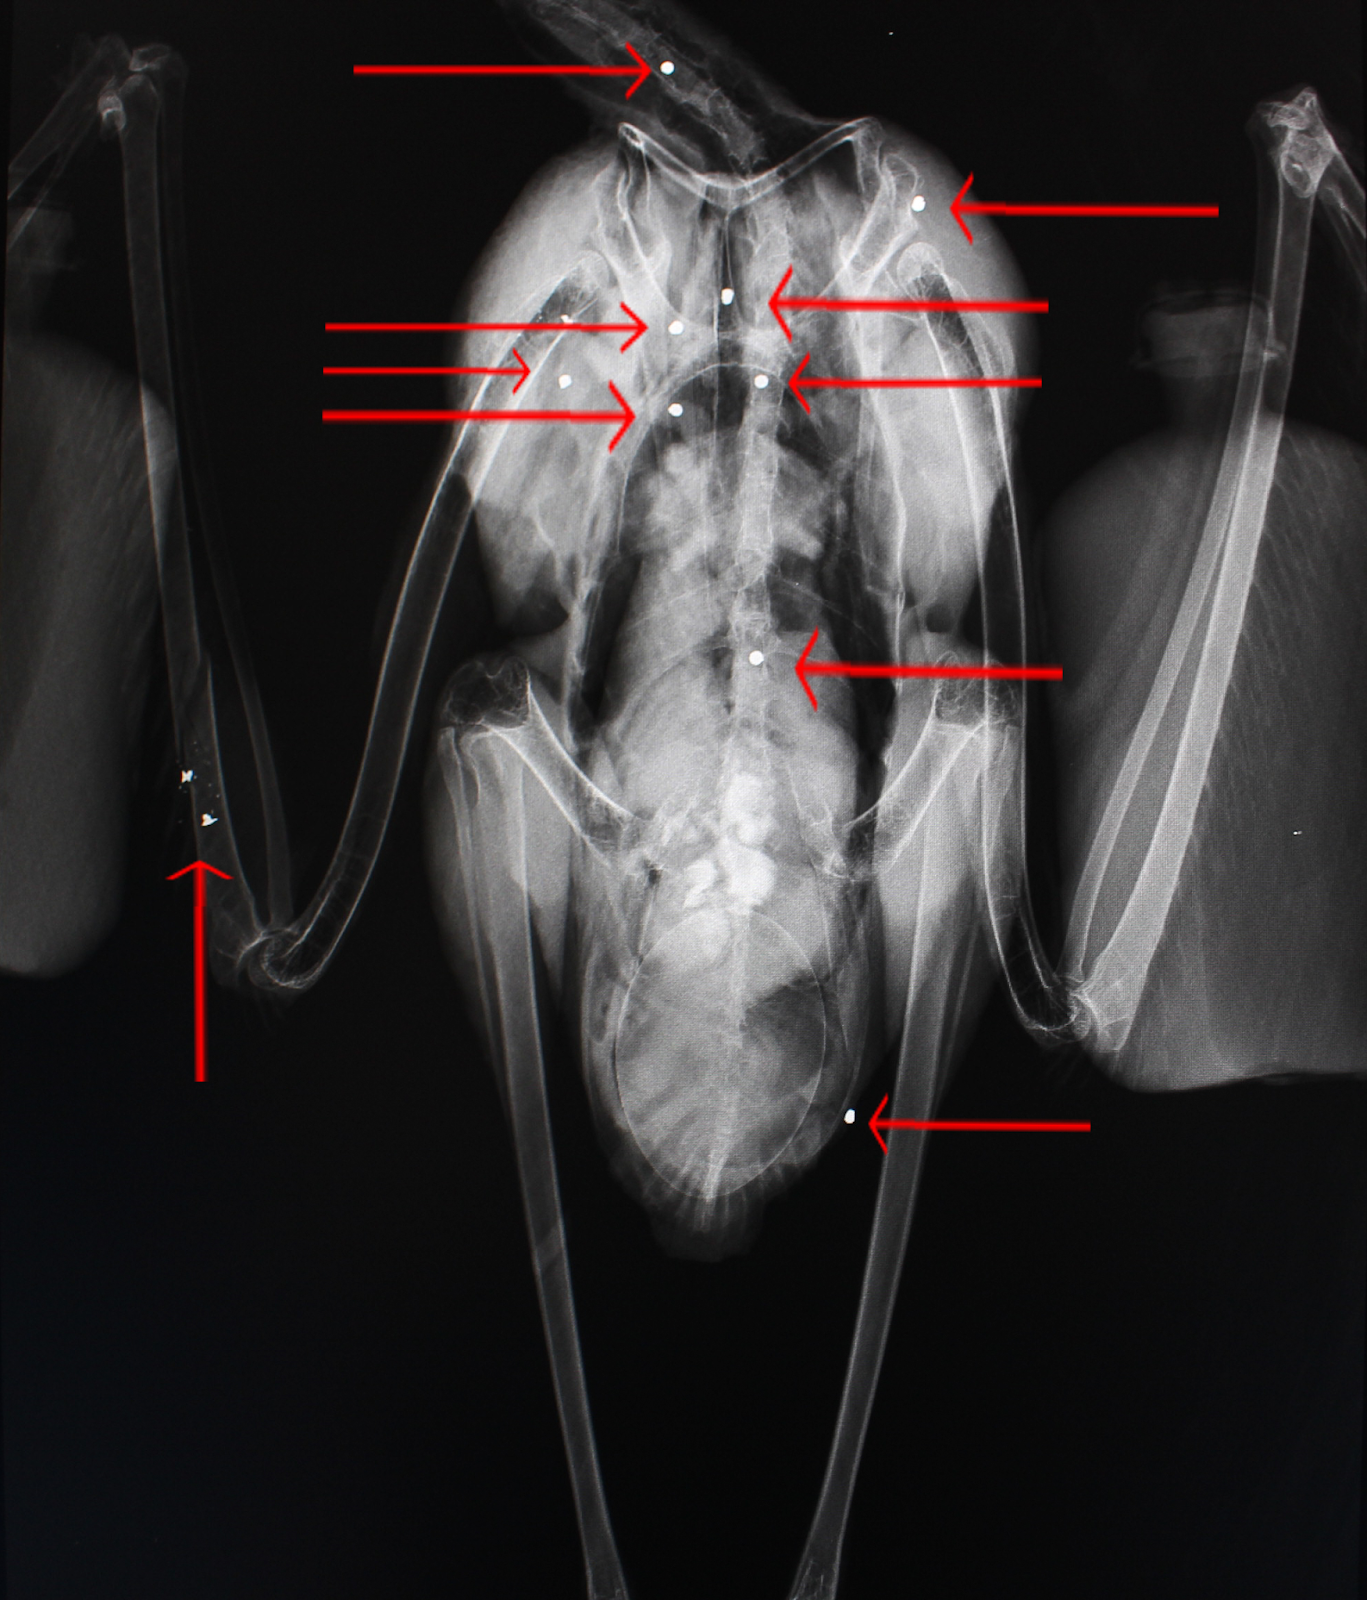

| Raio-X de uma gaivota com dois chumbos. |